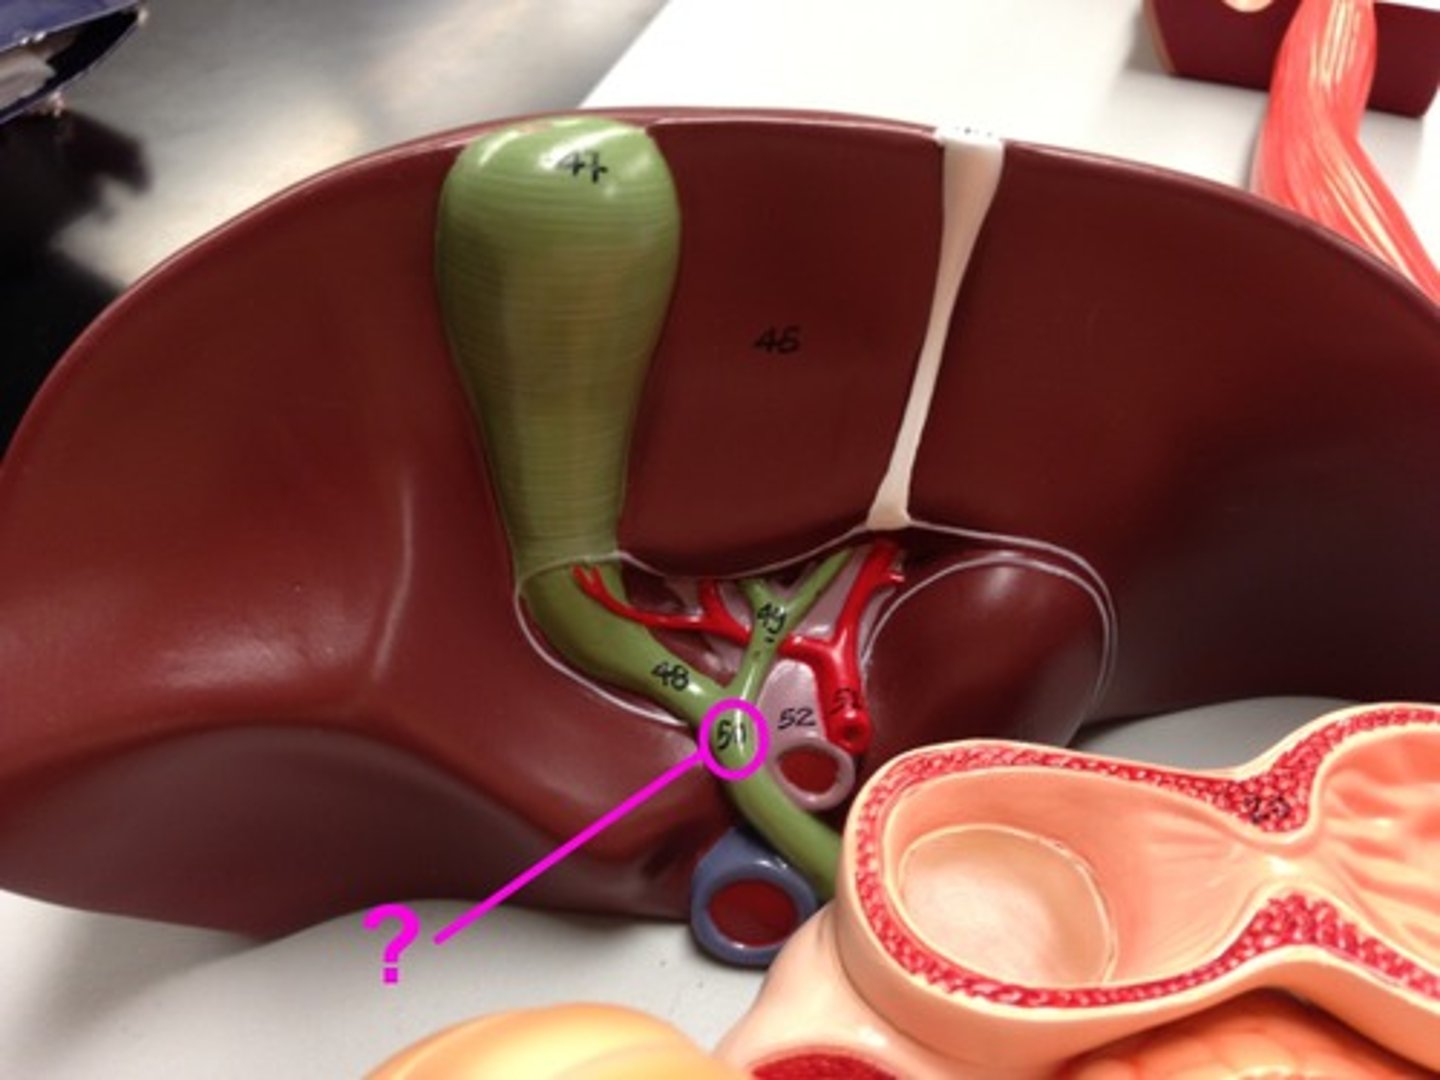

porta hepatis

where the blood and lymph vessels, bile ducts, and nerves enter and leave the liver

hepatic artery proper

common bile duct

common hepatic duct

cystic duct

hepatic portal vein

gallbladder

fundus (gallbladder)

body (gallbladder)

neck (gallbladder)